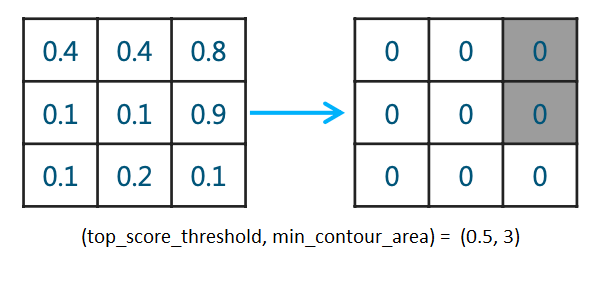

我们训练的分割模型输出每个像素的0-1概率,然后卡一下阈值,我们可以称这样的mask为basic sigmoid mask, 实际上医学图像中我们的分割目标也许并不存在,所以常用双重阈值(top_score_threshold, min_contour_area)的方法计算出mask并同时判断是否有分割目标(在本次比赛中我们分割目标是气胸),这种方法且称为doublet。其具体逻辑为:当大于概率阈值top_score_threshold的pixel数少于

min_contour_area,就将mask像素值全部置0,也就是认为此胸片没有气胸。简单画个示意图如下: